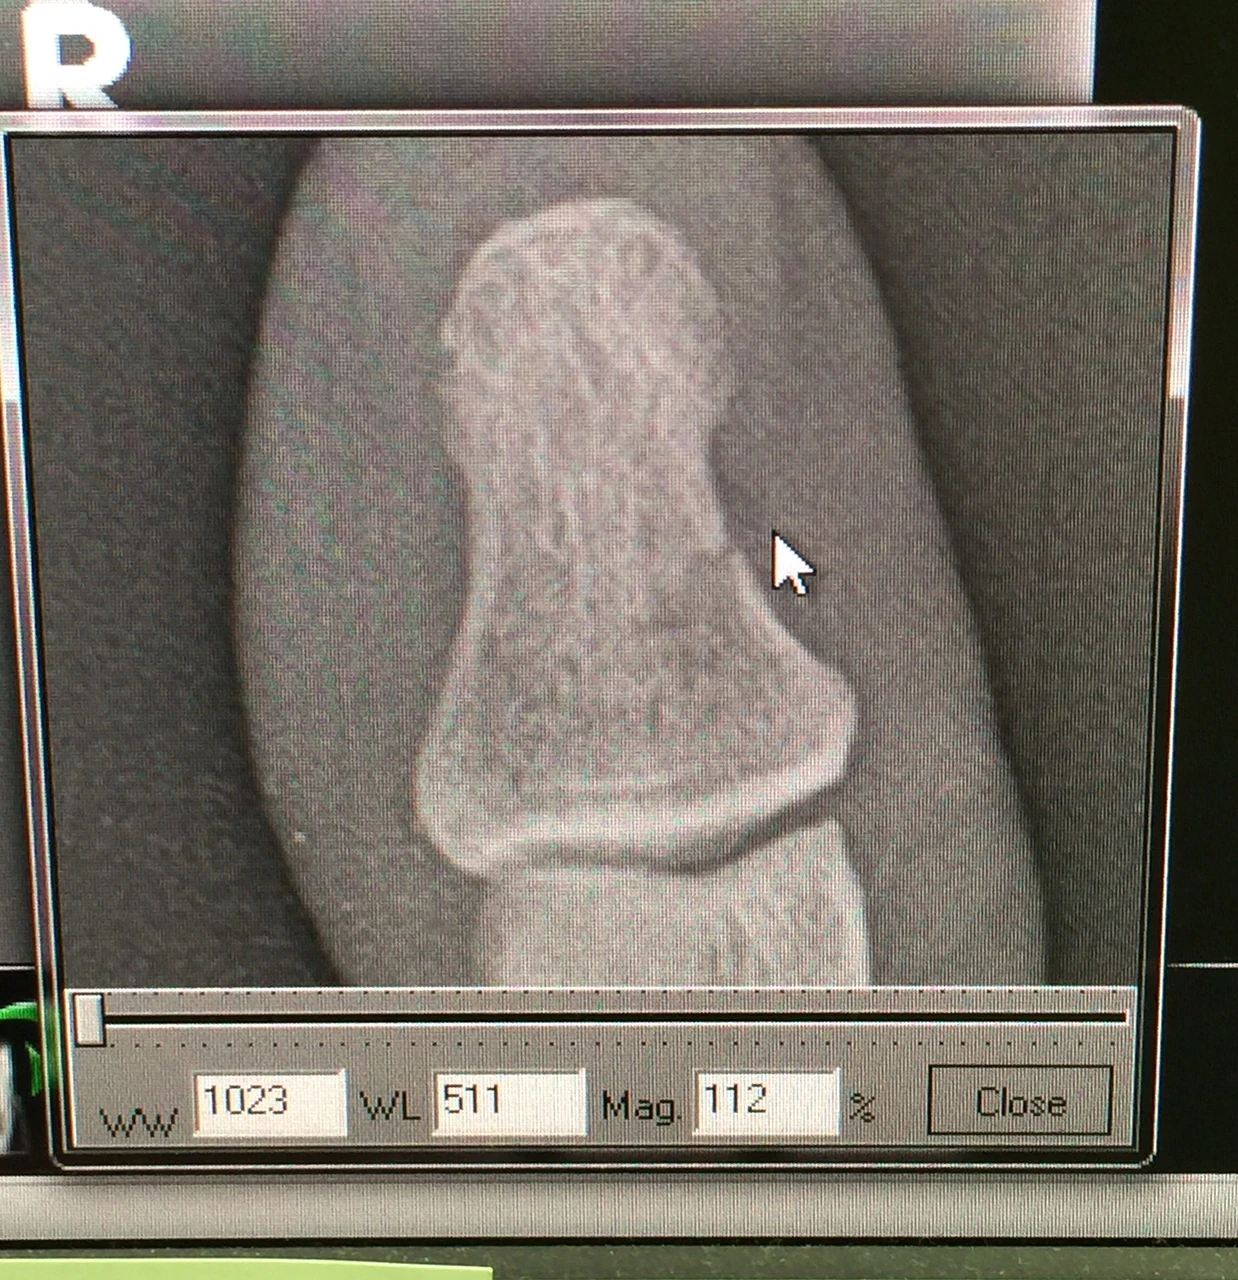

Last night my friend Stacie organized a Pro party for youth cyclocross here in Louisville. It is amazing the schedule that woman keeps. I had a little glimpse of some of her day yesterday and it was crazy. I went to her office mid day to get a x-ray of my thumb. Her office was a zoo. An organized zoo, crazy busy, but manageable, I guess. Turns out my thumb is broken. But, I knew that already. It still hurts pretty much, but nothing like it did 2 weeks ago. Plus, there is nothing that I have to do differently, so that is great. I came back to her house to get ready to ride. I was thinking I had all this time, but I didn’t realize that I hadn’t reset my watch from Chicago and it was off an hour. So all of a sudden 2:30 became 3:30. And the get together was starting at 6. I hurried and rode down the RIver Road over to the course. It had rained over an inch I hear, so expected it to be pretty soupy. At the bike wash, most of the bikes were pretty muddy, but not clogged up. But they were riding the whole course. I just rode the top section that serpentines up and down the hill. It was slick, but not muddy. I really didn’t put any effort into getting the lines down because it was going to be so much different today at 6. Anyway, I hightail it back to Prospect, which is 11 miles, and just get back in time to shower and get ready for the party. There were close to 100 people here. Lots of good food, wine, beer, etc. There were so many kids. And the U of Louisville cycling team had representation. There were a lot of really good riders that were on the panel for questions. Katie Compton, Ryan Trebon, Gage Hecht, Kaitlin Antonneau, Gavin Haley, Dan Timmerman, Jake Wells, Ally Stacher and a few others. It was super knowledgable group and there was a lot of information that was exchanged. Every race should have a meet and greet party like this. Today is going to be done in a blink. It is already late morning, I’m still on California time, and it is T-7 hours to race time. I’m going to suit up and do the 30 minute ride over to the course and do a couple laps between races. I have no illusions on how I’m going to do here. I very much doubt I’ll survive the 80% rule, which I think is bullshit. I haven’t seen the sandpit and am hoping it doesn’t jack up my drivetrain too much. Mike Crum left a comment yesterday about being unprepared for all the racing I’ve done. He is absolutely correct this time. I am super unprepared. I haven’t dismounted or mounted a cyclocross bike in two years and didn’t have enough time to get the correct equipment together for my liking. But I felt that I need to get back into the race scene and this was the first opportunity. I’ll be better in a month or so. The panel. The young guys had some great perspectives. The food was pretty impressive. Katie and I. Hip looks good. Buttons of my jeans are the dots. Broken thumb. Little hard to see the break in this picture, but it is pretty broke.